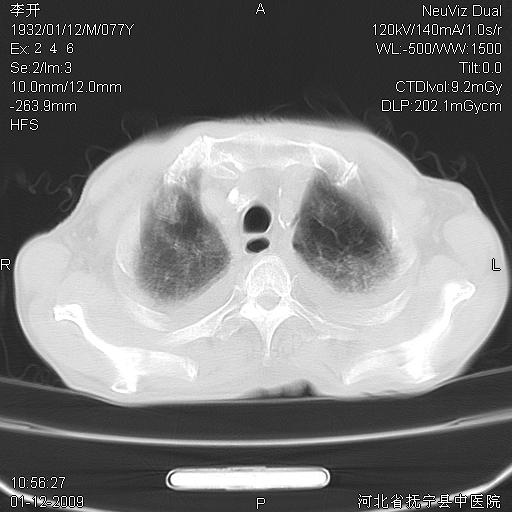

以下是引用黑白光影在2009-1-19 16:49:00的发言:[br]心衰肺水肿;心包、胸腔积液;冠脉钙化;肺部感染。